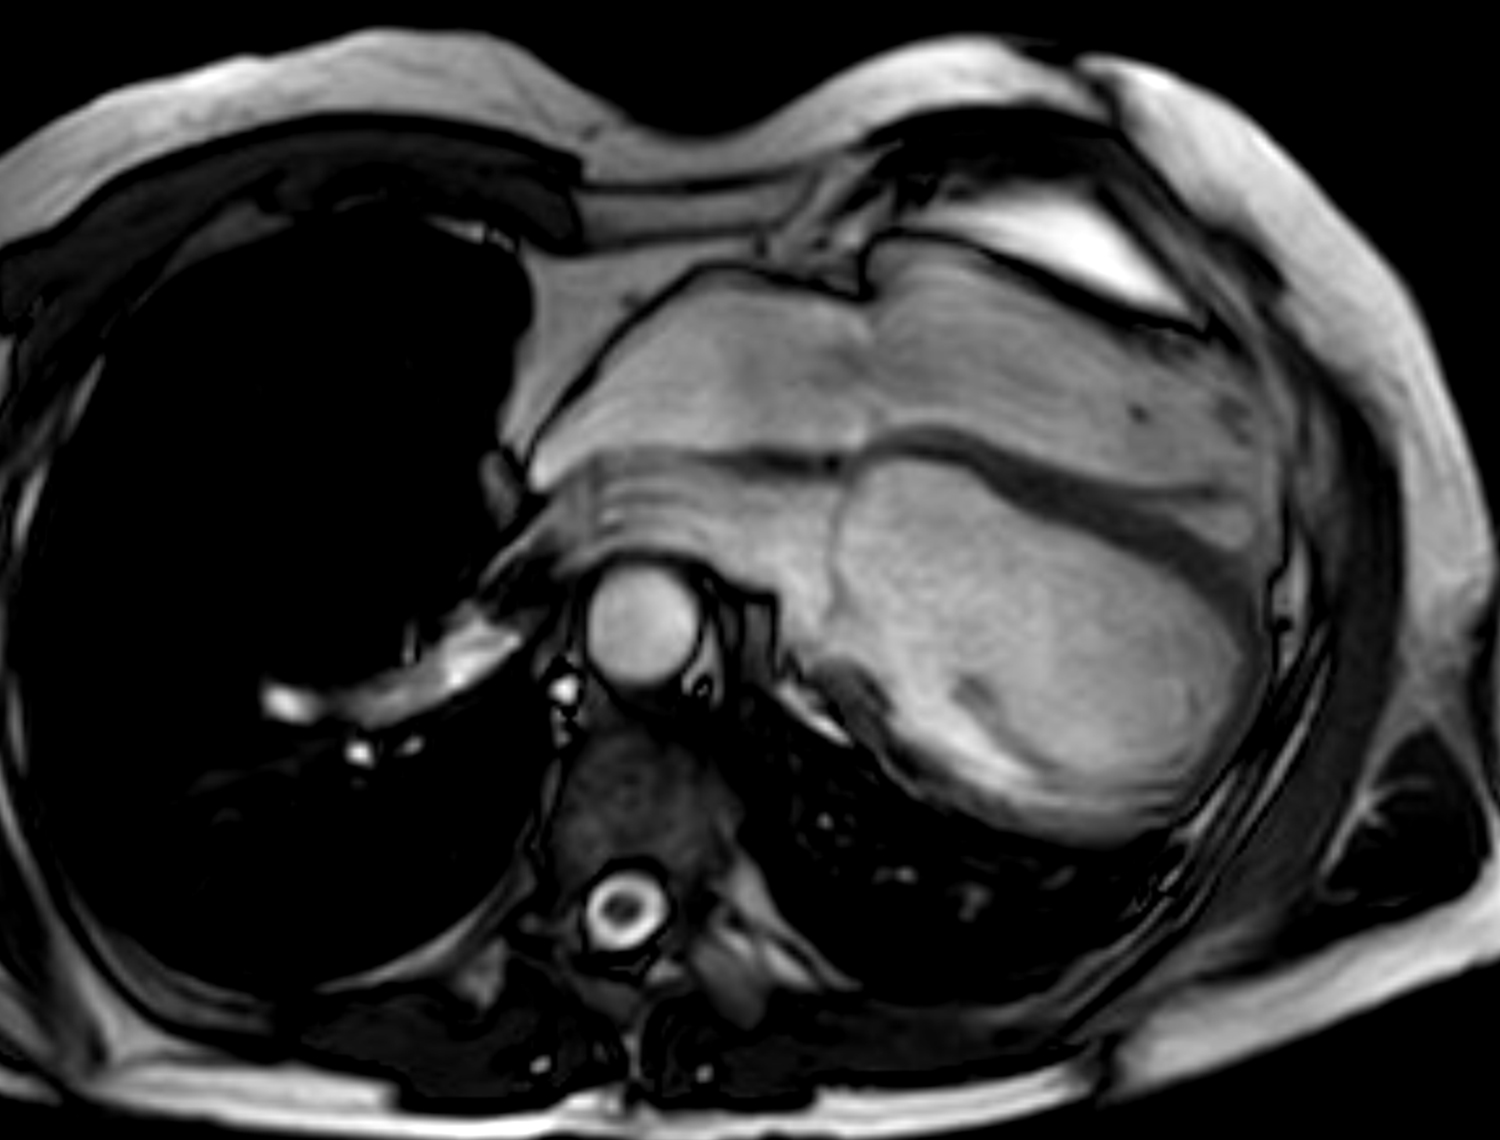

Pericarditis is classified based on duration of the acute episode—acute for those with pericarditis for less than 4 weeks; incessant for ongoing pericarditis between at least 4–6 weeks but less than 3 months without remission, chronic for pericarditis lasting for over 3 months, and recurrent pericarditis refers to 2 or more episodes of acute pericarditis with at least a 4–6 week interval without symptoms [1]. Recurrent pericarditis events occur in 15–30% after the first episode of pericarditis, and in 50% after 2 or more episodes [7, 8, 9, 10]. The diagnostic criteria for pericarditis based on guidelines include at least 2 out of the 4 criteria of (1) pericarditis chest pain, (2) pericardial rub on physical examination, (3) new ECG changes (widespread ST-elevation or PR depression) and new or worsening pericardial effusion; while other supporting features include elevated inflammatory markers (such as C-reactive protein, sedimentation rate and white cell count), and imaging evidence of pericardial inflammation (especially by MRI, Fig. 1) [1]. The main etiology categories of pericarditis are idiopathic, infective (most commonly viral, but also bacterial including tuberculosis, fungal and parasitic), autoimmune, iatrogenic (such as post-cardiac surgery and interventions), neoplastic, metabolic and drug-related. Tuberculosis pericarditis is mainly prevalent in developing countries and rare in developed countries.

Fig. 1.Multi-modality imaging features of acute pericarditis case. (A) Small pericardial effusion (arrow) subcostal view of echocardiography. (B) Pericardial thickening (arrow) on black-blood spin echo sequence of magnetic resonance imaging (MRI). (C) Severe circumferential increased pericardial signal indicating edema (arrow) on T2-weighted short tau inversion recovery imaging of MRI. (D) Severe circumferential pericardial enhancement indicating inflammation/fibrosis (arrow) on delayed gadolinium enhancement sequence of MRI.

Based on this criteria, echocardiography is the first-line imaging modality recommended for all patients undergoing pericarditis evaluation, although it is often normal [1, 2]. Apart from its main role in identifying pericardial effusion, echocardiography can examine the presence of tamponade physiology present in approximately 3% of acute pericarditis, identify pericardial thickening, evaluate for the presence of regional wall motion abnormalities that may indicate concurrent myocardial involvement (myo-pericarditis) in approximately 5%, or look for alternative diagnoses like acute coronary syndrome or aortic dissection [2]. Echocardiography is also important during follow-up after initial pericarditis event for resolution of pericardial effusion if it had been present, along with signs of constrictive physiology, discussed in the later section.

In contrast to echocardiography and MRI, CT has a limited role for evaluating pericardial inflammation. Pericardial thickening which may enhance of iodinated contrast and the presence of pericardial effusion may be observed on chest CT when there is pericarditis [11]. CT is however usually ordered for evaluating alternative causes of chest symptoms such as coronary artery disease, acute aortic syndrome, pulmonary thromboembolism and other lung pathologies [12]. In chronic pericarditis, CT can identify calcifications that may indicate the presence of constriction that should be confirmed by other imaging modalities [2].

Perhaps the most important application of MRI in pericardial diseases is its ability to identify pericardial inflammation [2, 10]. The key features include pericardial thickening, best assessed on black-blood spin echo sequences; pericardial edema, assessed using T2-short tau inversion recovery (STIR) sequences as high signal intensity; and inflammation or fibrosis on late gadolinium enhancement sequences again as high signal intensity (Fig. 1) [2, 13, 14]. Histologically, pericardial late gadolinium enhancement correlates with fibroblastic proliferation, neovascularization and chronic inflammation and granulation tissue [15]. Some studies have reported moderate sensitivity (63–68%) and high specificity (up to 100%) of the T2-STIR sequence for acute pericarditis, however this is significantly lower in practice, as elevated signal can also be seen with pericardial effusion or MRI artefact [16, 17]. The delayed enhancement sequence has been reported to have moderate to high 65–100% sensitivity and high specificity 99–100% for pericarditis, however again in practice this is lower with pericardial fat, pleuritis and artefact potentially interfering with scan interpretation, and fat saturated pulses added to delayed enhancement sequences are recommended to improve the positive predictive value of pericardial enhancement [14, 16, 17, 18]. MRI can also evaluate for concomitant myocardial involvement and inflammation (myocarditis) where they be left ventricular dysfunction and regional wall motion abnormalities on cine sequences; increased myocardial signal intensity on T2-STIR or elevated T2-mapping values implying myocardial edema; increased myocardial signal intensity on delayed gadolinium enhancement sequences or elevated T1-mapping values consistent with myocardial inflammation and fibrosis; and along with early gadolinium enhancement suggesting hyperemia [19]. As such MRI is strongly recommended in the initial diagnosis of pericarditis with a complimentary role to clinical, inflammatory biomarkers and echocardiography assessment, especially if the diagnosis remains uncertain after the other tests [1, 2, 10].